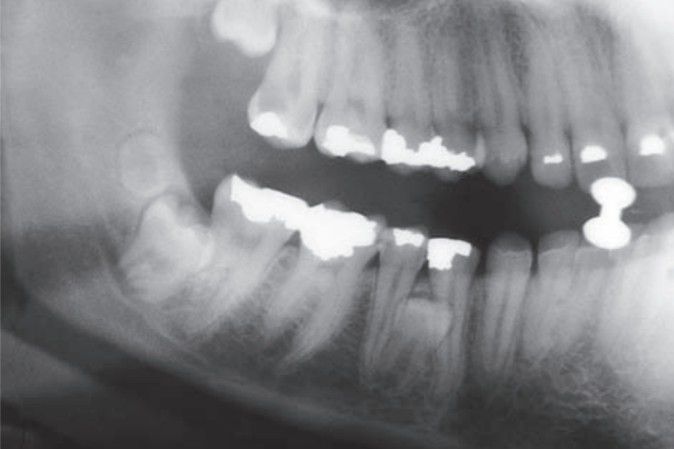

Supernumerary premolar

supernumerary, teeth in the dentition most probably result from continued proliferation of the permanent or primary dental lamina to form a third tooth germ